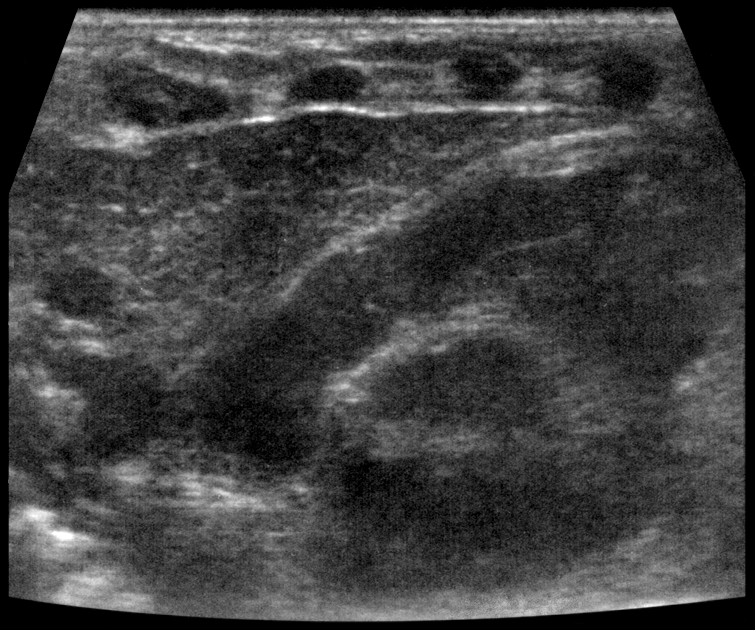

Тимомегалия: что это такое и как проявляется